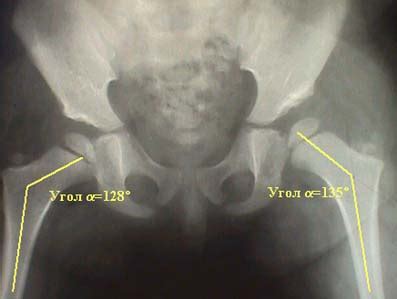

Рентгенанатомия

Справочные материалы Возрастные и половые показ...

Шеечно диафизарный угол тазобедренного сустава